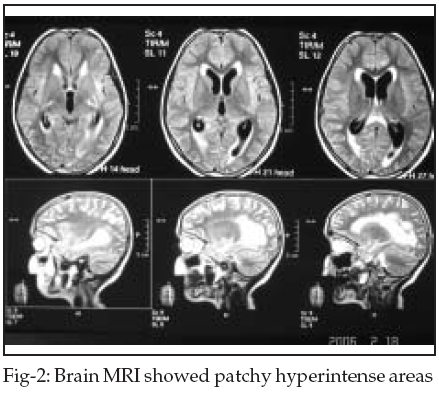

Brain CT revealed mild communicating hydrocephaly and brain MRI showed patchy hyperintense areas in pons, periventricular white matter, parietal, temporal, and frontal lobes in T2W images (Fig-1,2). At first with impression of Acute Disseminated Encephalomyelitis (ADEM), she was treated with methylprednisolon without any improvement. She developed fever and nuchal rigidity after third day of treatment and was referred to infectious ward.